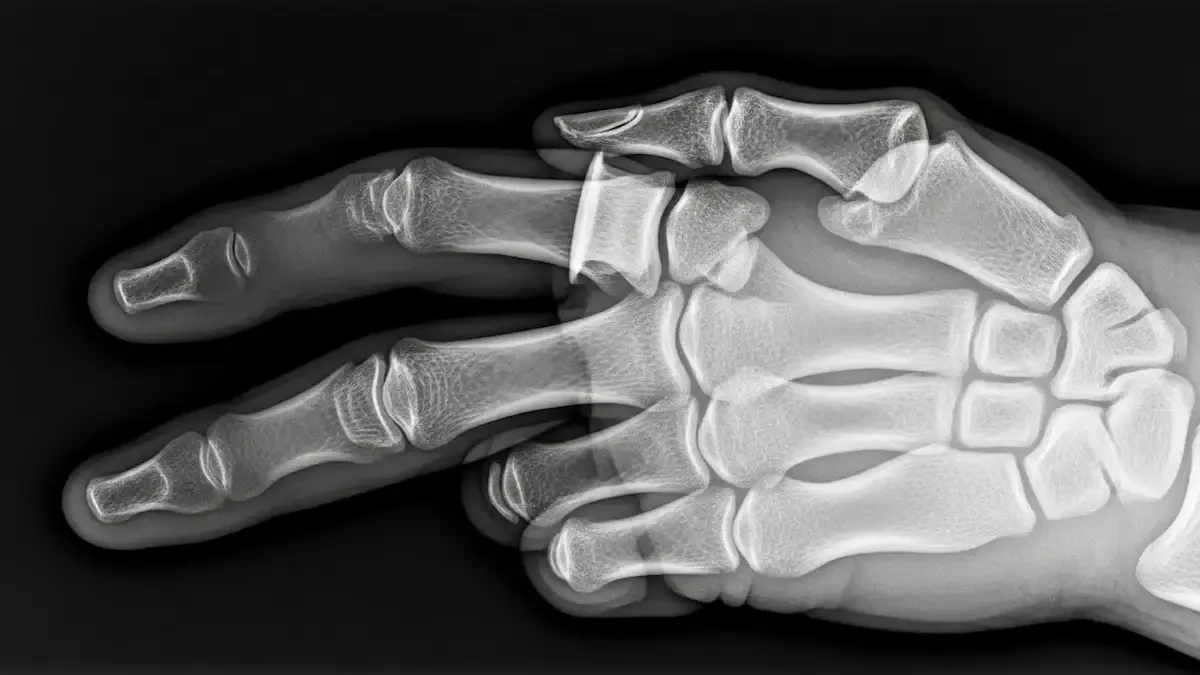

Como é feito o diagnóstico

O diagnóstico começa com o exame clínico, avaliando o alinhamento, a mobilidade e a estabilidade do dedo.

Radiografias em diferentes ângulos são solicitadas para confirmar a luxação e descartar fraturas associadas.

Em situações específicas, exames como a ressonância magnética ajudam a avaliar lesões ligamentares ou cartilaginosas.